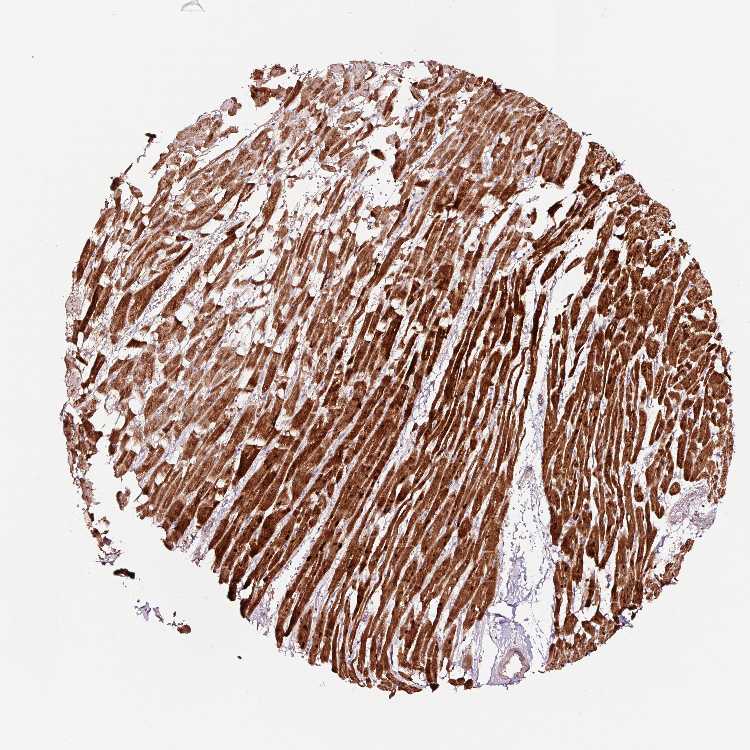

HEART MUSCLE - Antibody stainingi

Antibody staining in the annotated cell types in the current human tissue is reported as not detected, low, medium, or high, based on conventional immunohistochemistry profiling in selected tissues. This score is based on the combination of the staining intensity and fraction of stained cells.

Each image is clickable and will lead to virtual microscopy that enables deeper exploration of all samples and also displays staining intensity scores, fraction scores and subcellular localization as well as patient and tissue information for each sample.

Antibody HPA047089Antibody HPA053624

Cardiomyocytes HighHigh